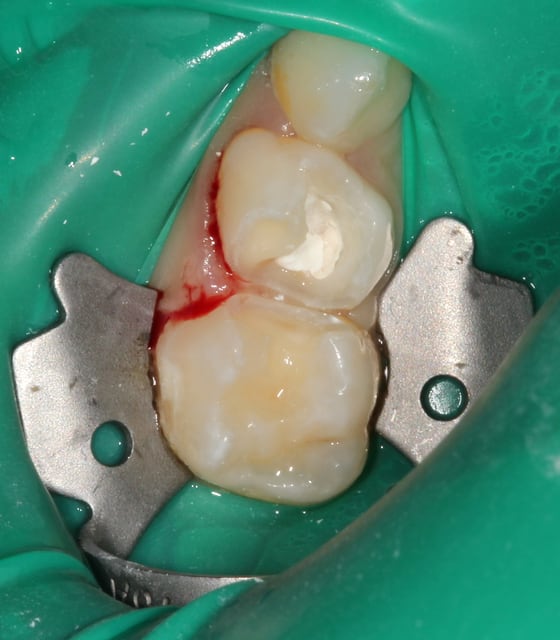

Oui. Les coins surtout sont parfaits car ils sont assez compressifs pour stopper tout saignements proximal, très fréquents chez l'enfant.

Je soigne exclusivement des enfants et toujours sous digue. Comme je te le disais plus haut : cela ne prend pas plus de 30 secondes et ce temps "perdu", tu le regagnes largement derrière.